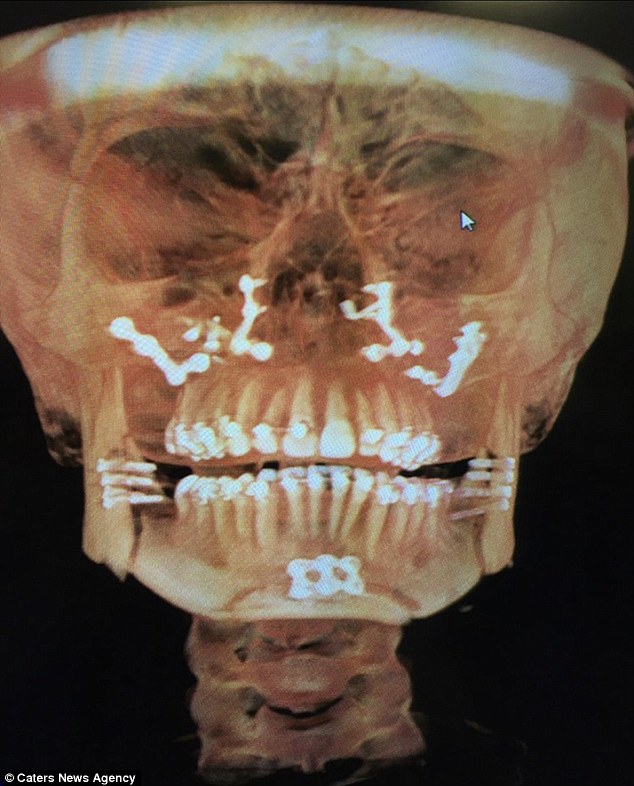

Para reparar la deformidad, a Lauren se le rompieron las dos mandíbulas y luego se volvieron a juntar usando 36 tornillos y hueso insertado en su barbilla. No solo la cirugía redujo el tamaño del mentón, ahora Lauren puede respirar adecuadamente y su ceceo ha desaparecido por completo.

Debido a la magnitud de la deformidad de Lauren, la cirugía tomó nueve horas cuando debería haber tomado cuatro.

La recuperación de Lauren fue muy complicada, debido a que el injerto óseo falló y causó infección, lo que llevó a una cirugía adicional. Otro hueso también se agrietó, lo que llevó a un tercer procedimiento.